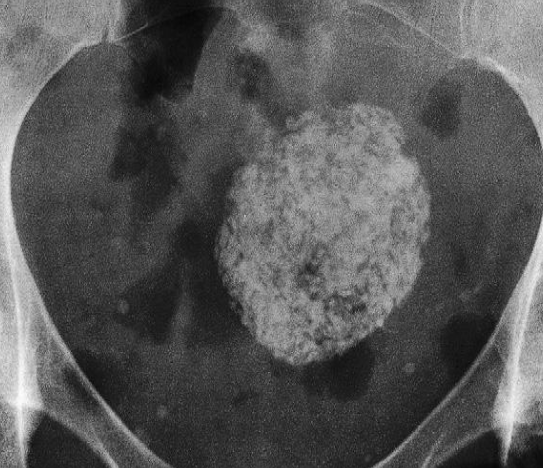

Calcified Uterine Leiomyoma

Plain radiograph:

- Calcification in a large uterine fibroid